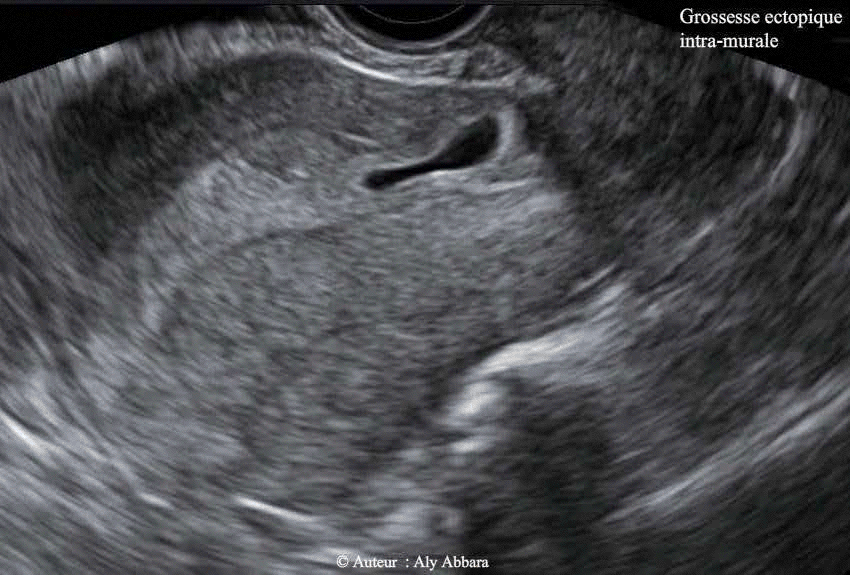

• Images échographiques par voie endovaginale montrant un sac gestationnel d'une grossesse débutante et partiellement intramurale, implantée dans le site de la cicatrice de l'hystérotomie segmentaire transversale d'une ancienne césarienne.

• A l'âge de 5+2 SA ; le sac gestationnel mesure 20 x 12 x 8,5 mm de diamètres (= 1,1 cm3) ; le dosage de β-hCG plasmatique était égal à 13 583 UI/l.

• Cette échographie a été réalisée juste avant le début du traitement médical par l'administration de méthotrexate (1 mg/kg soit 75 mg) par voie intramusculaire.

Le 04.10.2012 (5+2 SA) -J0- : la patiente consulte aux urgences pour légère douleur pelvienne sans métrorragie ; l'examen clinico-échographique permet de mettre en évidence le diagnostic d'une grossesse débutante implantée dans le site de l’ancienne cicatrice de l’hystérotomie segmentaire transversale de l'ancienne césarienne ; il s'agissait d'un sac gestationnel de (20 x 12 8,5 mm) de diamètre, contenant une vésicule vitelline sans image embryonnaire.